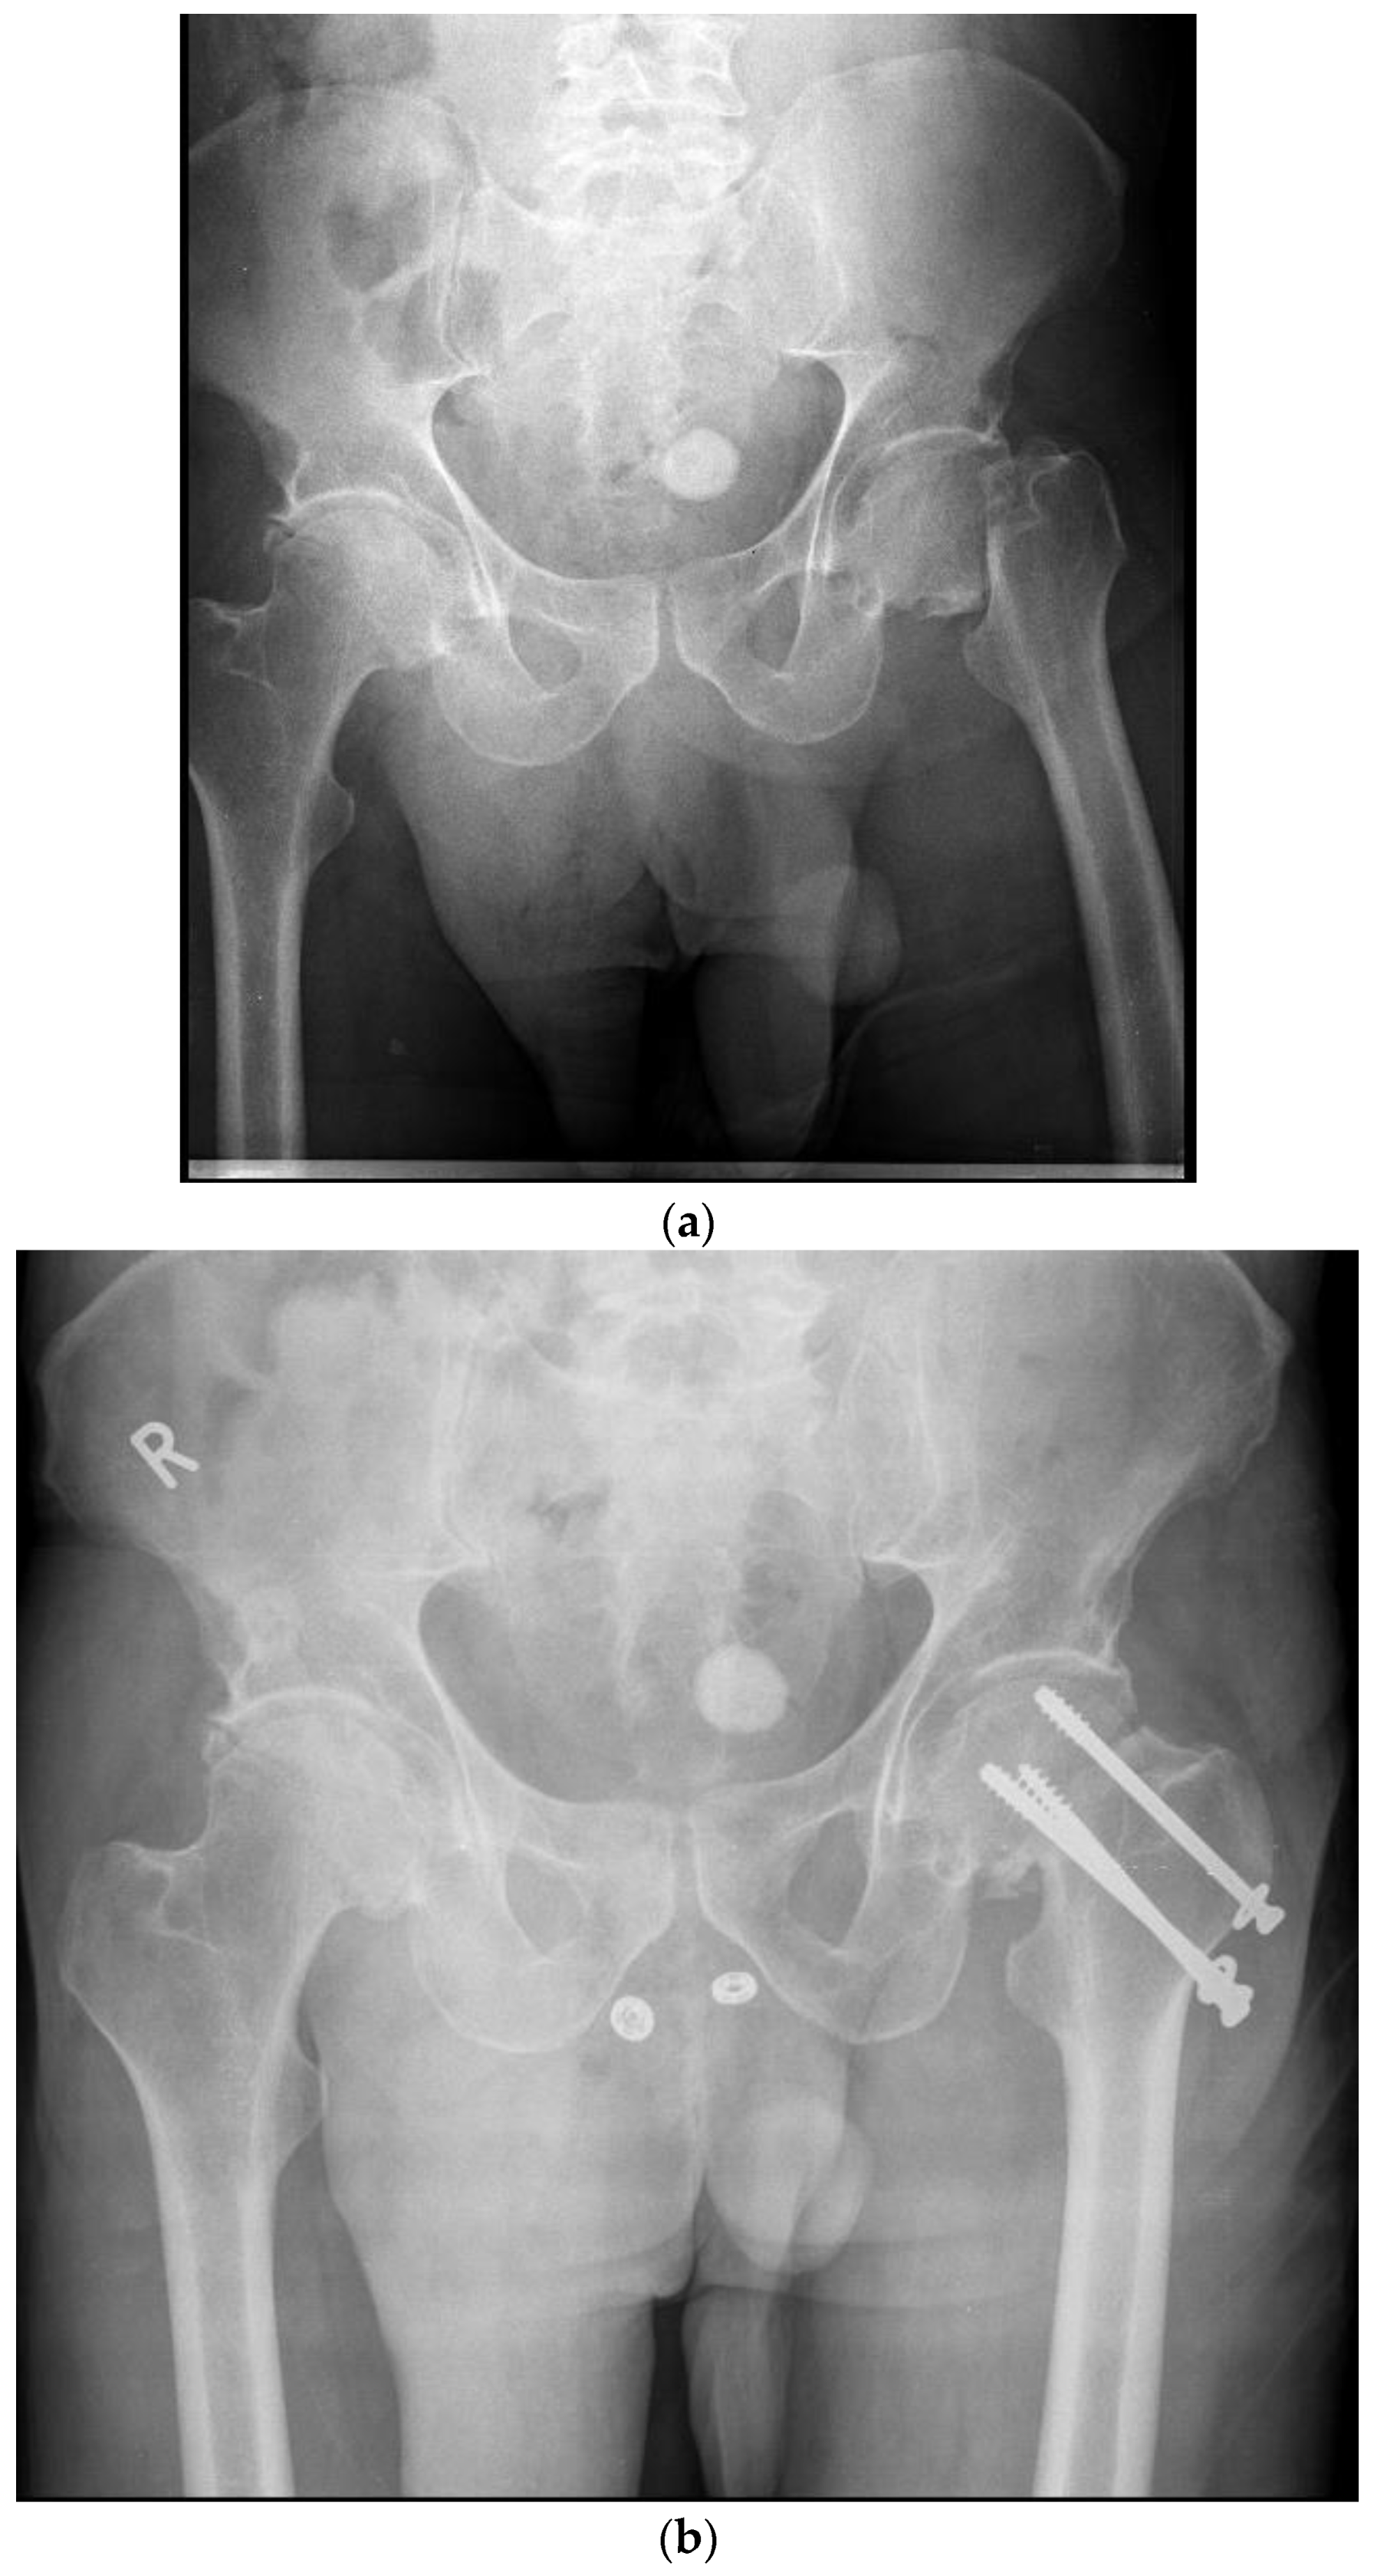

Figure 2. A- Pre-operative X-Ray demonstrating a left sided displaced femoral neck fracture in a 48-year-old male. B- post- operative X-Ray demonstrating operative fixation of the same fracture with the Targon FN system.